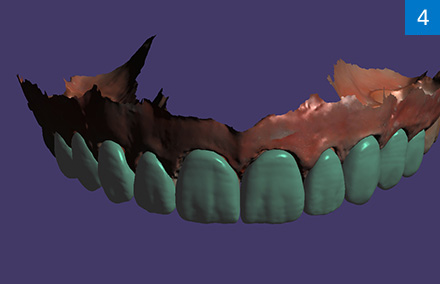

Après un nettoyage dentaire, une radiographie en trois dimensions (DICOM) a été réalisée, et des modèles virtuels générés individuellement et en occlusion (STL) à l'aide d'un scan intra-oral. Les deux jeux de données ont été appairés afin de tenir compte du niveau osseux et des tissus mous de la dent dans le cadre de CEREC Smile Design et de la construction qui en résulte. Les restaurations des 42 et 41 avec des facettes et des 33 et 31 avec des couronnes en VITABLOCS TriLuxe forte devaient, sur cette base de planification virtuelle, niveler en une séance la partie mandibulaire antérieure.

Pourquoi VITABLOCS TriLuxe forte ?

La céramique feldspathique VITABLOCS TriLuxe forte était le bon choix dans ce cas : c'est en effet le matériau CFAO par excellence lorsqu'il s'agit d'obtenir une couleur et une translucidité parfaitement adaptées. Le système de colorants et de glaçure VITA AKZENT Plus a permis d'obtenir une personnalisation satisfaisante pour le patient. Réalisées au laboratoire du cabinet, les quatre restaurations ont pu être mises en place par collage en une seule séance.

L'absence de la 32 avait entraîné une version à la mandibule.

Étant donné la présence d'une inflammation locale, un nettoyage dentaire initial a été effectué.

La mandibule a été scannée, et un modèle virtuel généré.

Mâchoires supérieure et inférieure virtuelles en articulation avec le logiciel CEREC Smile Design.

Les restaurations ont été conçues à l'aide de CEREC Smile Design.

Restaurations en VITABLOCS TriLuxe forte mises en place sur les 33, 31, 41 et 42.